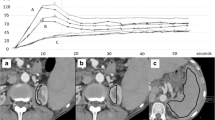

The dual input maximum slope model [15] was used for perfusion analysis of the liver. Two methods were used with regard to the settings of the regions of interest (ROIs) in all patients. In Method I the ROIs were manually placed in the abdominal aorta, the portal vein, the spleen and normal liver parenchyma to generate respective time-density curves (TDCs). The generated TDCs represented the hepatic artery input function and the portal vein input function, respectively (Fig. 1A). The peak point of the generated TDC of the spleen is used to separate the hepatic artery circulation before the peak point and the portal vein circulation after the peak point, respectively. In Method II the break point was manually set at the crossing point of the aortal and portal venous TDC (Fig. 1B). This adapted method was performed as it has been shown that in patients with portal venous hypertension peak splenic enhancement may be delayed, which may alter perfusion measurements due to inaccurate separation of arterial and portal venous perfusion [16]. Hepatic arterial blood flow (HAF; ml/min/100 ml), portal venous blood flow (PVF; ml/min/100 ml), as well as the hepatic perfusion index (HPI; HAF/(HAF + PVF); %) were calculated for all liver segments and the results were averaged for the whole liver.

(A–D) Dual input maximum slope model of the liver yielding time-density-curves (TDC) for the aorta, the portal vein, the spleen and the liver (A, B) and parametric images (C, D) for hepatic arterial flow (HAF; left top), portal venous flow (PVF; right top) and hepatic perfusion index (HPI; left bottom) as well as corresponding pre-contrast grey-scale images (right bottom). The peak point of the TDC of the spleen is used to separate the hepatic artery circulation before the peak point and the portal vein circulation after the peak point, respectively. In patients with cirrhosis, the TDC of the liver may be flattened with a delayed peak (A). Perfusion calculation with this setting led to very low PVF and very high HPI (C). Manual adaptation with placement of the breakpoint at the crossing point of the aortal and portal venous TDC (B) led to significantly higher PVF and lower HPI (D). HAF, PVF and HPI in this patient were 68.5 ml/min/100 ml, 51.2 ml/min/100 ml and 61.4% for the standard setting (A, C), and 71.4 ml/min/100 ml, 126.5 ml/min/100 ml and 38.1% for the manual adapted setting (B, D). Severe portal hypertension (HVPG 22 mmHg) may contribute to the flat shape of the splenic TDC in this patient. SP start point, EP end point, SM spleen maximum

Using different ROI settings for separation between HAF and PVF led to significant differences in PVF and HPI calculation in our patients. This is in accordance with a study by Fischer et al. [16], which showed that peak splenic enhancement, which defines the break point between HAF and PVF, is delayed in patients with PH, resulting in a miscalculation of hepatic perfusion parameters. The authors recommended using peak renal enhancement instead of peak splenic enhancement in patients with PH. In our study, the break point was manually set at the crossing point of the aortal and portal venous TDC, which indicates the time point of replacement of the HAF by the PVF. We believe that this may be a more accurate method for hepatic blood flow separation than using a ROI within the renal parenchyma.